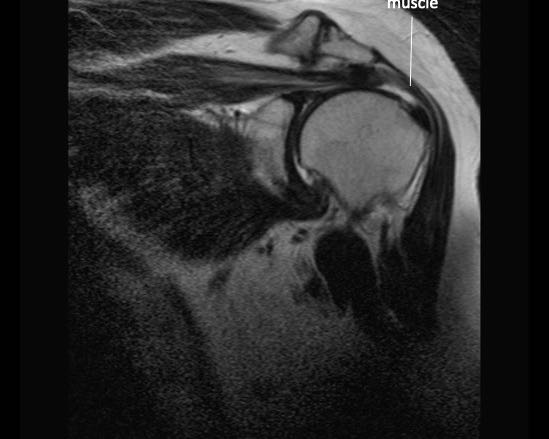

Rách toàn bộ chiều dày hoàn toàn

Nhấp vào hình ảnh để phóng to, sau đó cuộn qua các lát cắt.

Có hình ảnh rách toàn bộ chiều dày gân cơ trên gai kèm co rút và teo cơ.

Lưu ý các dải mỡ trong cơ tròn bé, cơ trên gai và cơ dưới gai.